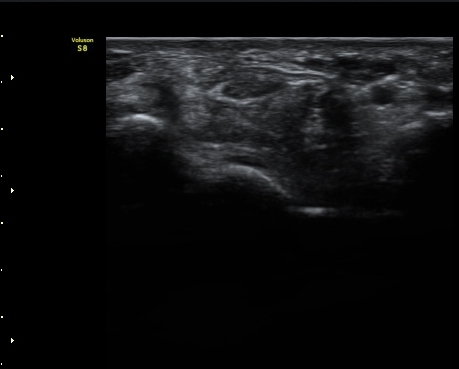

ŽÃËÀÚ¸¦ Á¶±Ý ´õ ¸»´ÜÀ¸·Î À̵¿ÇÏ´Ï Á¤Áß½Å°æ ½ÉºÎ¿¡ Àú¿¡ÄÚ ³¶Á¾ÀÌ °üÂûµÇ°í(»çÁø 4),

³¶Á¾ÀÌ Á¤Áß½Å°æ ¼öÁö °¡Áö¸¦ ¾Ð¹ÚÇÏ´Â ¸ð½ÀÀÌ °üÂûµÈ´Ù(»çÁø 5, 6, 7).